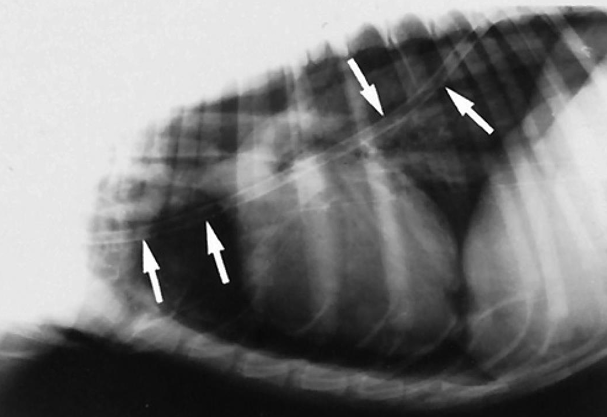

![]() | sternal lymph node 폐결절이면 이렇게 벽에 딱 붙어있진 않을 것 |

![]() | mast cell tumor가 화살표 쪽에 전이됨. (cranial mediastinal lymphadenopathy) |

![]() | - Cranial mediastinal(위쪽) - Sternal (아래쪽) |